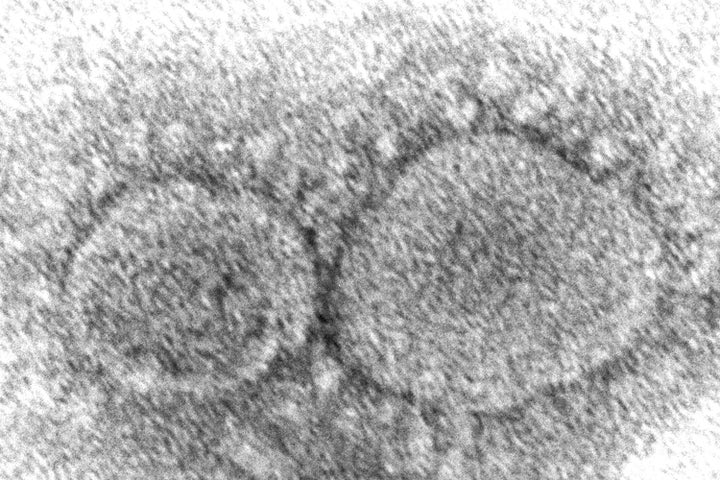

Επανέρχονται στο προσκήνιο οι θερωρίες «διαρροής του ιού από κινεζικό εργαστήριο».

Το Υπουργείο Ενέργειας των ΗΠΑ (DOE) πρόσφατα αξιολόγησε με «μικρή σιγουριά» ότι ξεκίνησε από εργαστήριο, σύμφωνα με έκθεση που δεν έχει δει ακόμη το φως της δημοσιότητας.

Ενώ ορισμένοι επιστήμονες είναι ανοιχτοί στη θεωρία της διαρροής από εργαστήριο, άλλοι συνεχίζουν να πιστεύουν ότι ο ιός προήλθε από ζώα, μεταλλάχθηκε και μεταπήδησε στους ανθρώπους - όπως συνέβη στο παρελθόν με άλλους ιούς. Οι ειδικοί λένε ότι η πραγματική προέλευση της πανδημίας μπορεί να μην είναι γνωστή για πολλά χρόνια - αν γίνει ποτέ γνωστή.